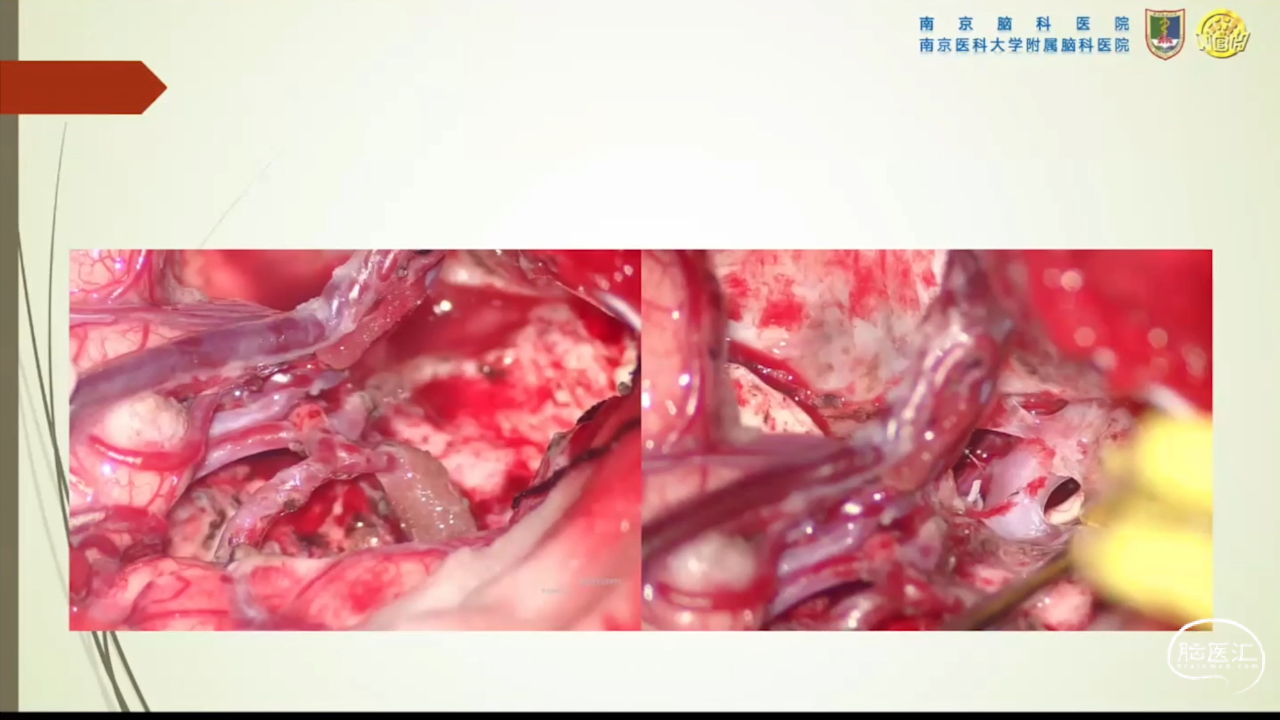

胶质瘤是发病率最高的颅内肿瘤(约占44.69%),岛叶是神经胶质瘤的好发部位,大约有25%的低级别胶质瘤及10%的高级别胶质瘤发生在岛叶,大多数岛叶胶质瘤为低级别胶质瘤。岛叶在调节内脏感觉运动、控制心血管交感活性、传入躯体感觉中均起重要作用。它也参与了痛觉的传递、运动规划、自主性吞咽、味觉、听觉、前庭功能、情绪、认知能力和语言能力。因为岛叶解剖结构复杂,并覆盖有高级语言皮层、白质束及重要的血管结构,故岛叶部位的手术难度极大。

会议内容截图